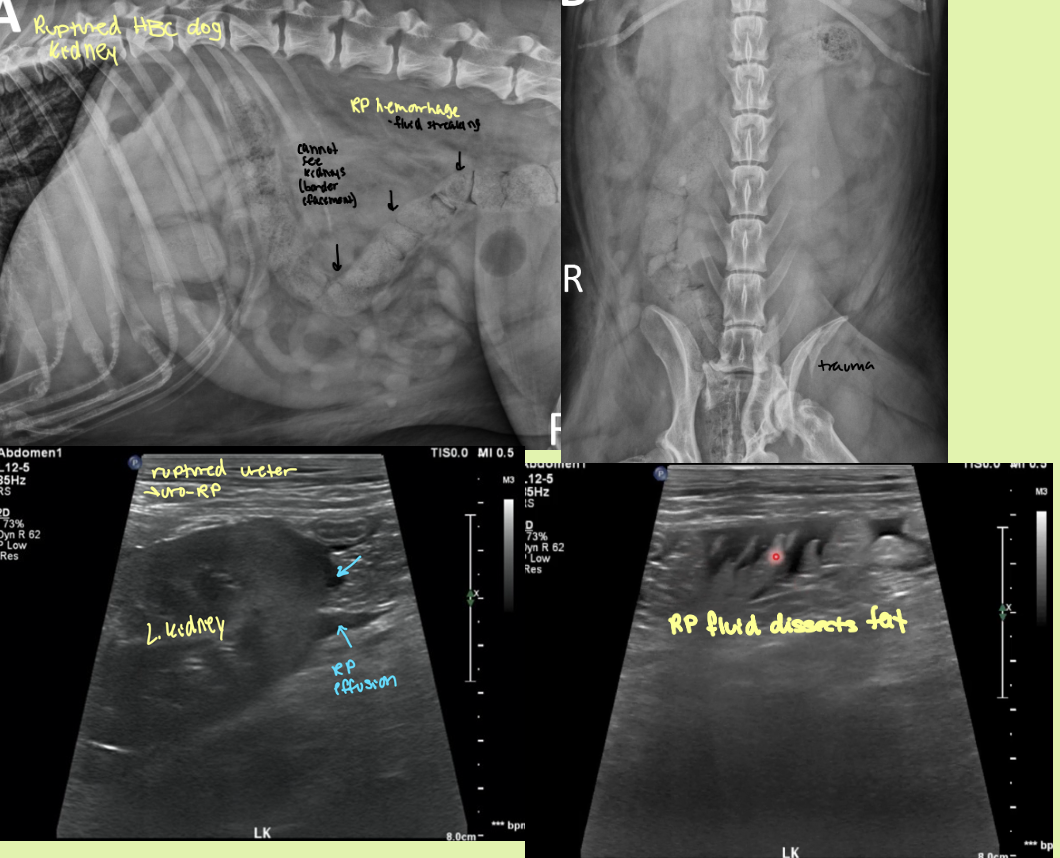

what is the best mode of imaging for a ruptured kidney

EU

fluid opacity in the RP region that makes it hard to make out the kidneys. EU has leakage of contrast into RP space and a hematoma is seen on ultrasound

ruptured kidney

rad and ultrasound findings of ureteroliths

Rad findings - Can be seen

Ultrasound findings

hyperechoic structures with distal acoustic shadowing

Variable size

If obstruction—> hydronephrosis and hydroureter prox. and a normal ureter distally